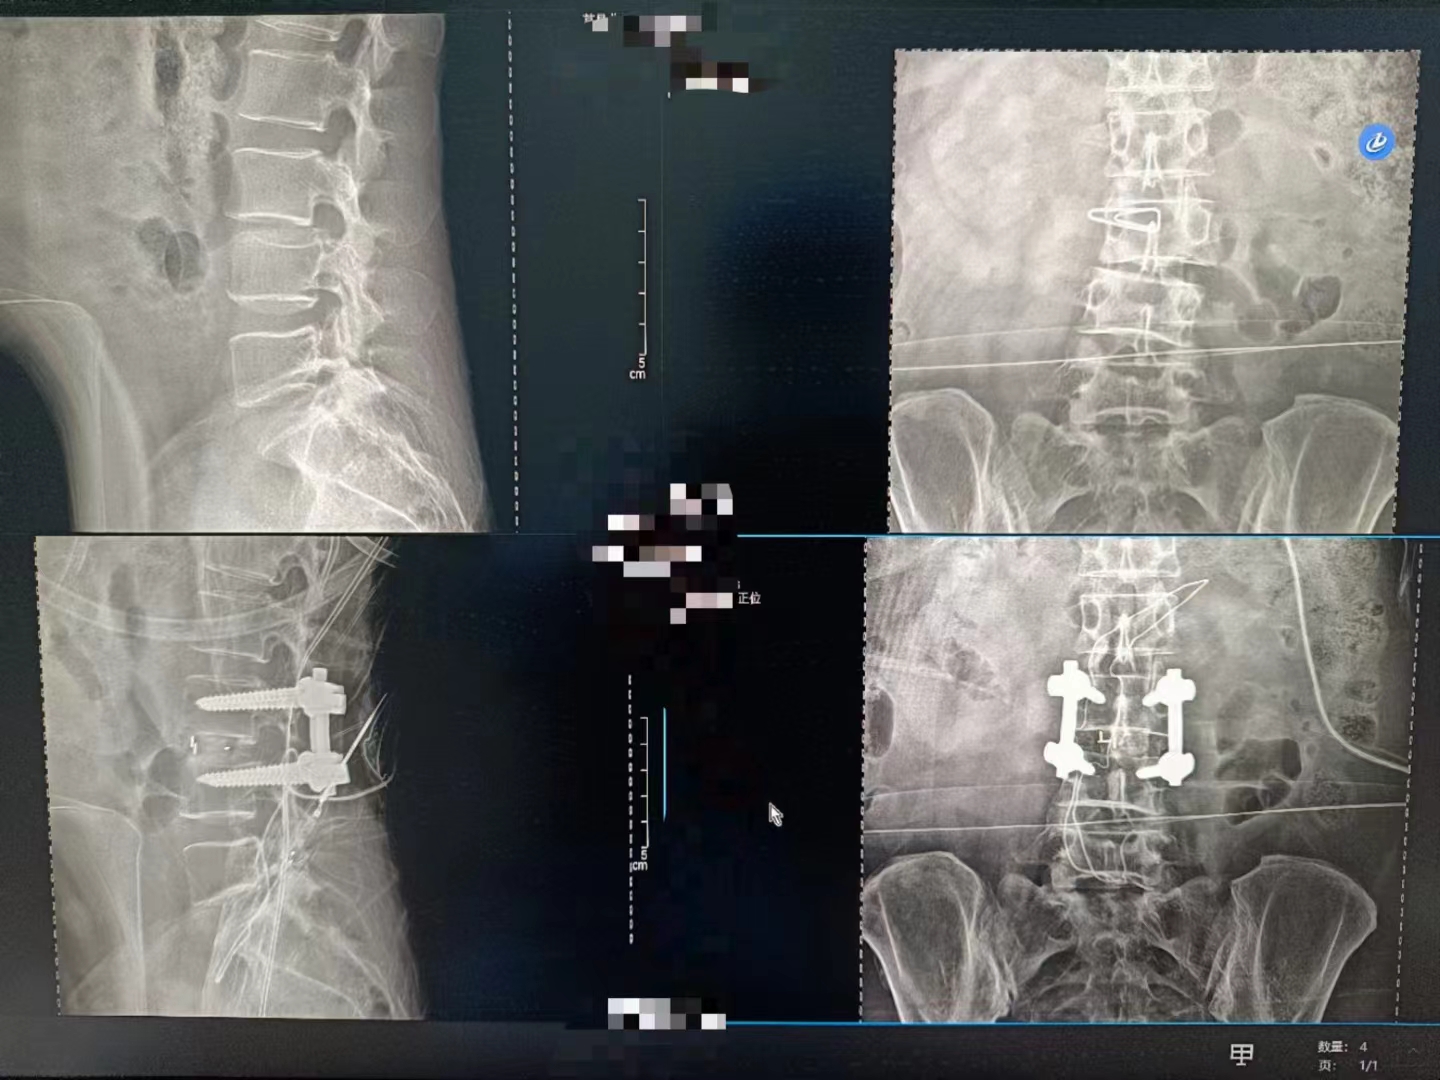

當設備啟動,那束柔和的X射線穿過患者的身體,捕捉下每一個細微的影像。那一刻,時間仿佛凝固,所有的目光都聚焦在那塊屏幕上。那里,生命的紋理清晰可見,疾病的陰影無處遁形。

手術順利完成,當醫(yī)生們露出疲憊而欣慰的笑容時,我知道,那不僅僅是勝利的喜悅,更是對生命的敬畏與珍視。而這一切,都離不開這臺數字化X射線攝影設備的默默付出。